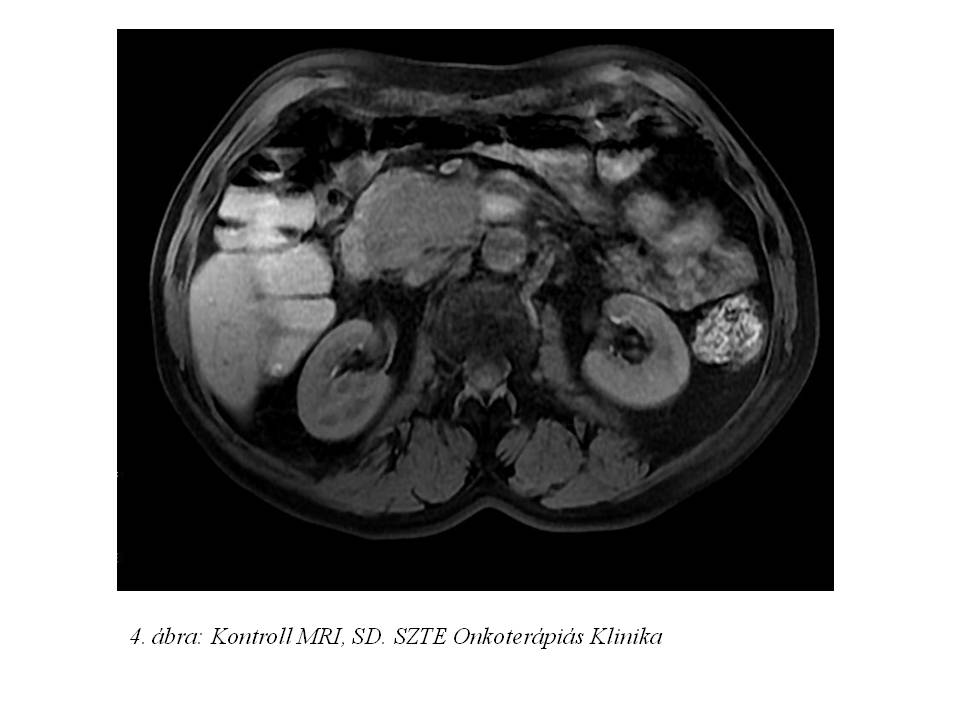

2013.06.15-től octreotid terápiát indítottunk. A pontos staging érdekében octreoscan vizsgálat (3. ábra) is történt, mely a pancreas fej területén, valamint a májban és a has területén több helyen is kóros aktivitásfokozódást igazolt. Az octreotid kezelés alatt folyamatos re-staging vizsgálatok történtek, kezelését 15 hónapig tartottuk (4. ábra).